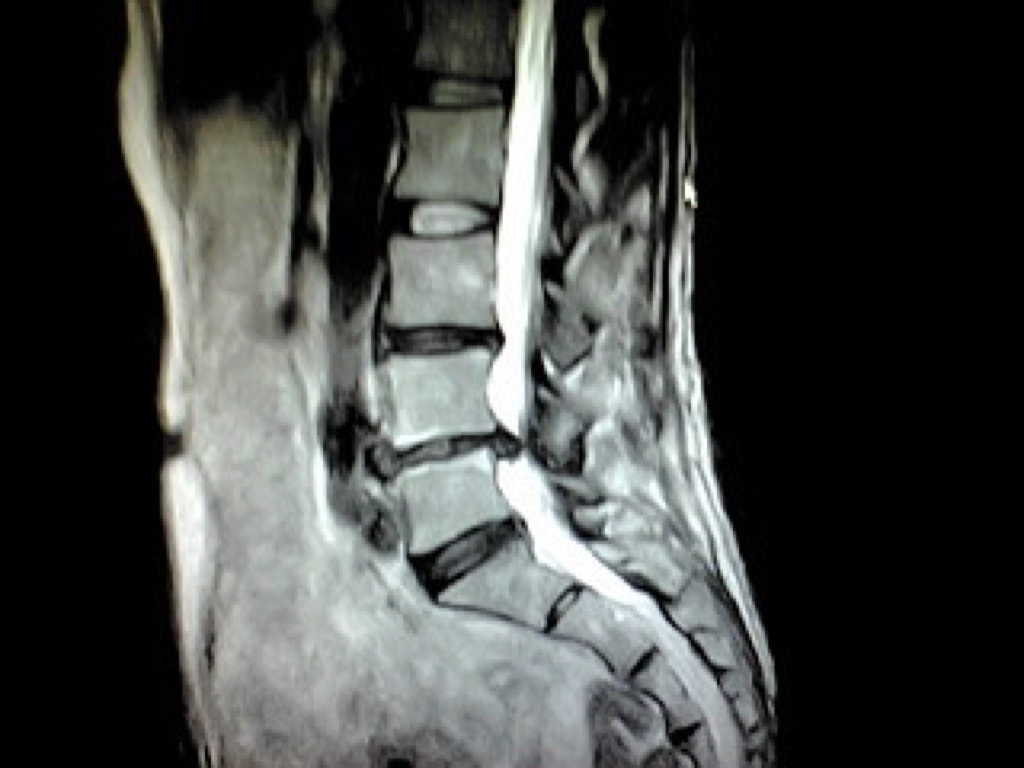

病気の早期発見のために、最新のMRIを用いた本格的な検診。

大病院などで用いられている最新のMRIを使用し、精度の高い結果を得、かつ痛みや不快感を極力排除することを可能にしました。